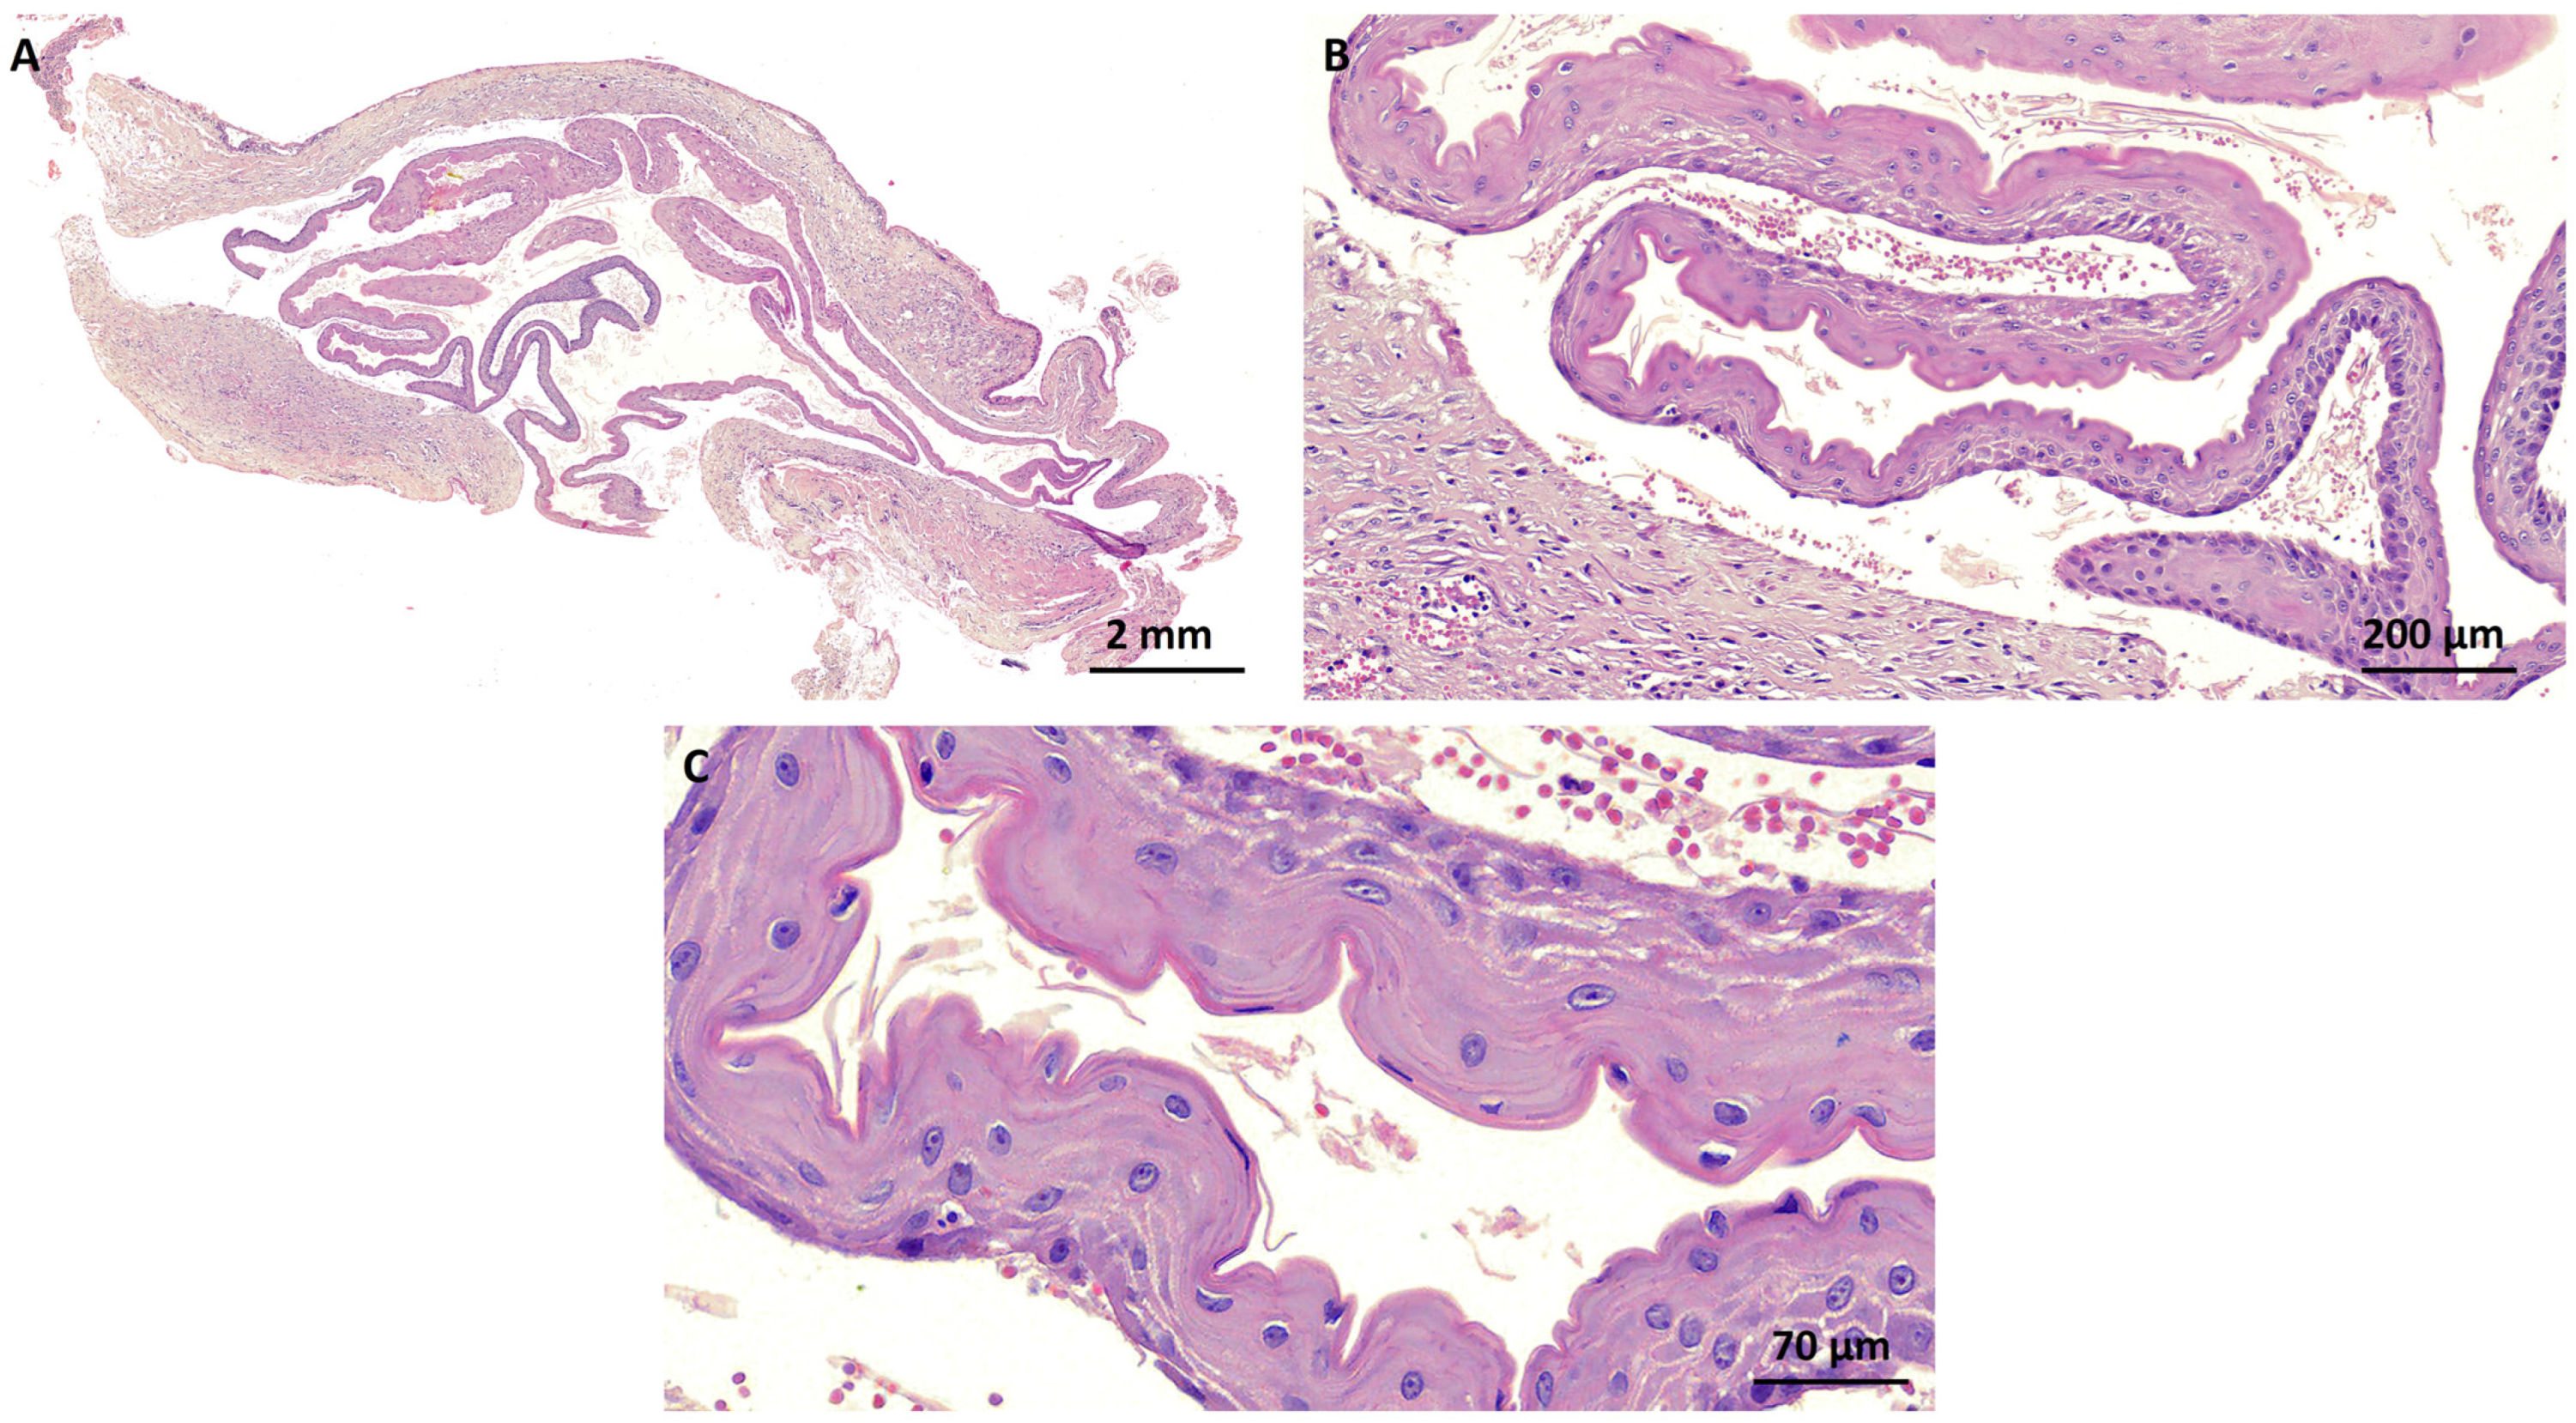

2. Case Report